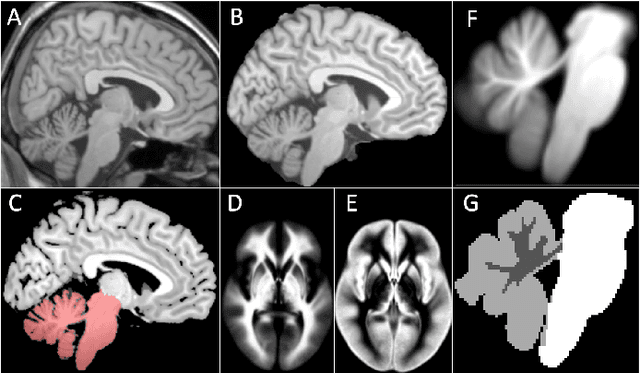

Abstract:Surgical resection is a common procedure in the treatment of pediatric posterior fossa tumors. However, surgical damage is often unavoidable and its association with postoperative complications is not well understood. A reliable localization and measure of cerebellar damage is fundamental to study the relationship between the damaged cerebellar regions and postoperative neurological outcomes. Existing cerebellum normalization methods are not reliable on postoperative scans, therefore current approaches to measure surgical damage rely on manual labelling. In this work, we develop a robust algorithm to automatically detect and measure cerebellum damage due to surgery using postoperative 3D T1 magnetic resonance imaging. In our proposed approach, normal brain tissues are first segmented using a Bayesian algorithm customized for postoperative scans. Next, the cerebellum is isolated by nonlinear registration of a whole brain template to the native space. The isolated cerebellum is then normalized into the spatially unbiased atlas (SUIT) space using anatomical information derived from the previous step. Finally, the damage is detected in the atlas space by comparing the normalized cerebellum and the SUIT template. We evaluated our damage detection tool on postoperative scans of 153 patients diagnosed with medulloblastoma based on inspection by human expects. We also designed a simulation to test the proposed approach without human intervention. Our results show that the proposed approach has superior performance on various scenarios.